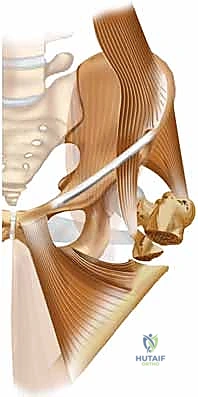

لفهم طبيعة الكسر وكيفية عمل التسمير النخاعي، يجب أن نتعرف على تشريح عظمة الفخذ، وهي أطول وأقوى عظمة في جسم الإنسان. ينقسم الجزء القريب من عظمة الفخذ (Proximal Femur) إلى عدة مناطق رئيسية:

1. رأس الفخذ (Femoral Head): الجزء الكروي الذي يستقر في تجويف الحوض ليُشكل مفصل الورك.

2. عنق الفخذ (Femoral Neck): المنطقة الضيقة التي تربط الرأس ببقية العظمة، وهي عرضة للكسور خاصة عند كبار السن.

3. المدور الكبير والمدور الصغير (Greater and Lesser Trochanters): نتوءات عظمية بارزة تعمل كنقاط ارتكاز واتصال للعضلات القوية المحركة للورك والفخذ.

4. منطقة ما تحت المدورين (Subtrochanteric Region): الجزء من العظمة الذي يقع أسفل المدور الصغير مباشرة، وهو يتحمل ضغوطاً ميكانيكية هائلة أثناء المشي.

كسور هذه المنطقة تُعرف طبياً بكسور ما بين المدورين (Intertrochanteric Fractures) أو كسور ما تحت المدورين (Subtrochanteric Fractures). ونظراً للضغوط الهائلة التي تتعرض لها هذه المنطقة، فإن تثبيتها يتطلب غرسة قوية قادرة على تحمل الوزن، وهو ما يوفره المسمار النخاعي الرأسي الفخذي بكفاءة عالية.

التسمير النخاعي الرأسي الفخذي هو تقنية جراحية متطورة تعتمد على مبدأ "تقاسم الحمل الميكانيكي" (Load-Sharing Device). بدلاً من تثبيت شرائح ومسامير على السطح الخارجي للعظم (والتي قد تنكسر تحت ضغط الوزن)، يتم إدخال سيخ أو مسمار طويل وقوي مصنوع من سبائك التيتانيوم الخالص داخل التجويف النخاعي (المركزي) لعظمة الفخذ.

يتكون هذا النظام الجراحي من:

1. المسمار النخاعي الرئيسي (Intramedullary Nail): مسمار طويل يمتد داخل القناة النخاعية لعظمة الفخذ.

2. المسمار الرأسي/العنقي (Cephalic/Lag Screw): مسمار سميك وقوي يمر من خلال الجزء العلوي للمسمار النخاعي، ويدخل في عنق ورأس عظمة الفخذ لتثبيت الكسر الرئيسي.

3. مسامير الغلق السفلية (Distal Locking Screws): مسامير صغيرة تُثبت أسفل المسمار النخاعي لمنعه من الدوران أو الانزلاق داخل العظم.

هذا التصميم العبقري يجعله أقوى نظام تثبيت متوفر حالياً، حيث يمر محور تحمل الوزن عبر المسمار الموجود داخل العظم، مما يجعله مقاوماً للكسر والانحناء، ويسمح للمريض بالاعتماد على ساقه في وقت قياسي.